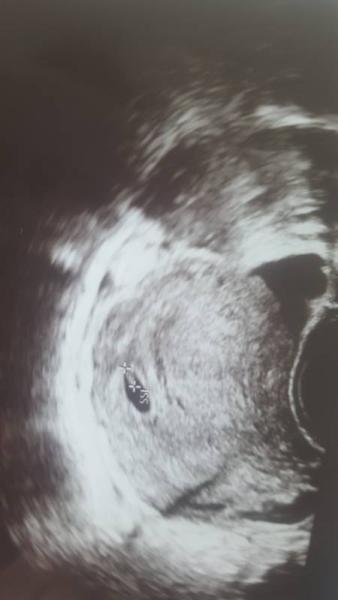

Huhu,also alles super ,sitzt in der gebärmutter ,Herz schlägt ,und mehr sieht man noch nicht in der 7 SSW:-D Aber bis jetzt alles Top ! War sowas von nervös

Bild zu Zurück vom Frauenarzt :-) 😍 - Forum für Januar - Mamis